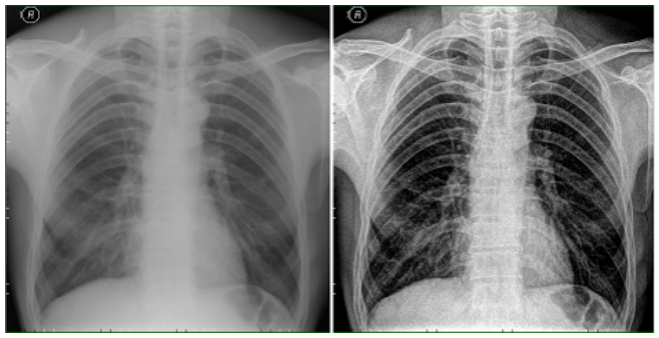

局部处理(CR):

原始图像经普通边缘增强后的效果

通过多尺度对比度增强技术可成功应用在PACS系统针对X-ray图像的处理过程中。图像中不同尺寸的低对比度细节的视觉质量显著改善,这种处理方式不会产生严重的边界效应(振铃效应),这一优点使得此技术能够广泛应用于CT、MR、DR、CR、数字乳腺诊断等成像。